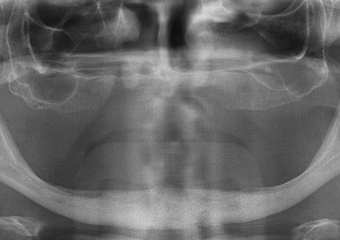

Raio X inicial